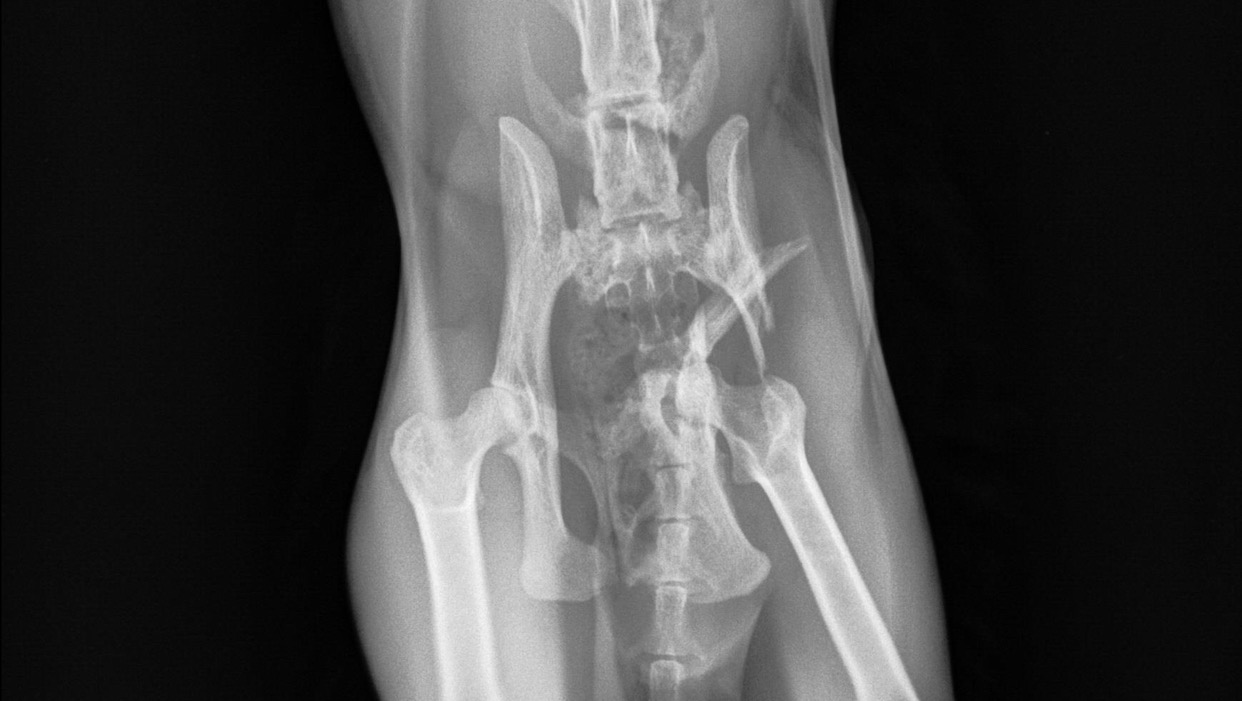

He can’t put any weight on his left hind leg, and even at the pelvis his leg looks misaligned. I’m already anticipating he will need at the very least an X-ray and a cast, maybe a surgery and medicine. I need help raising funds in anticipation of what I’m sure will be a high vet bill.